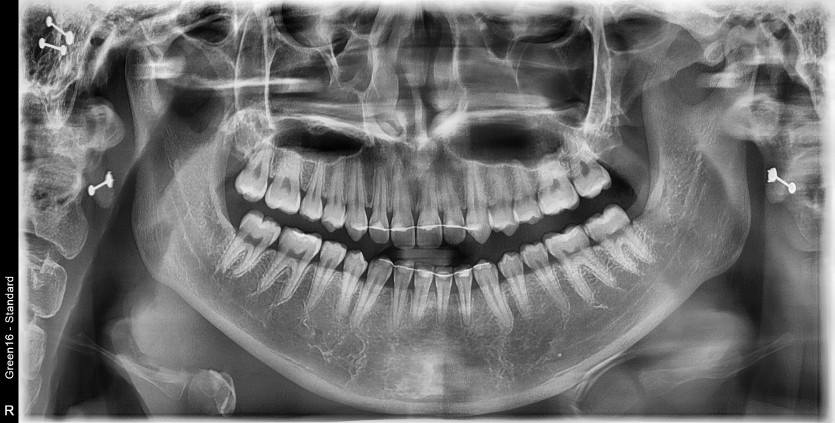

#28,38 사랑니 발치

구강 외과 전문의가 당일 발치했습니다.